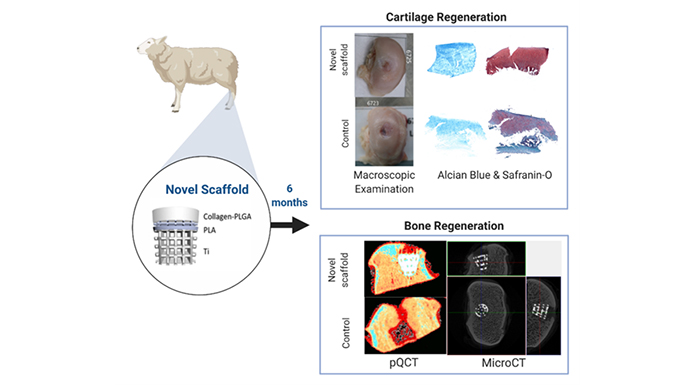

To this end, researchers at University College London (UCL) have invented a novel multi-layered osteochondral scaffold system which works with the body’s natural mechanisms to bear the load of the joint while encouraging the regeneration of cartilage and bone tissue. This novel scaffold incorporates both organic and inorganic material to make it customisable to each patient, a quality which, when scaled-up, would be an impressive advance for precision medicine, improving outcomes and the longevity of replacement joints and reducing the costs and risk factors of the knee and hip surgeries.

Both rabbit and sheep condyle model studies have demonstrated that the osteochondral scaffold achieved a stable mechanical fixation when implanted into the osteochondral defect of the joints – the bone grew into the titanium matrix and formed strong support to the overlying cartilage regeneration which led to the improved cartilage fill and healthy growth as revealed by histological examinations. The scaffold is designed for use with large bones like the knee, hip, and shoulder, but is flexible enough to be adapted to work with any joint in the body, large or small. Osteochondral scaffolds can be used to repair large cartilage defects in osteoarthritis patients to either delay the need for or act as a cost-effective alternative to joint replacement and will help patients to lead a more active and pain-free lifestyle.